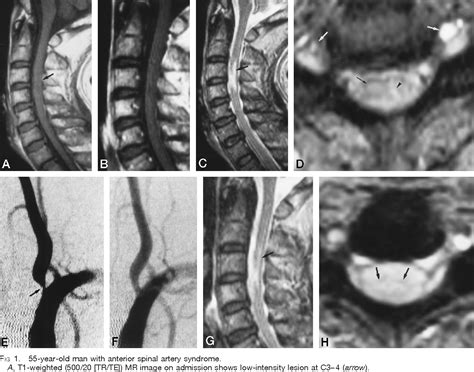

• Imaging Studies: MRI or CT scans to visualize the spinal cord and identify the location and extent of the injury.